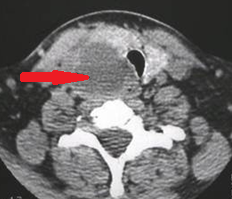

Neck CT. Red arrow — Large cyst on the right, compressing the esophagus, with well-defined margins and colloid content (Courtesy Dr. V. Penopoulos)